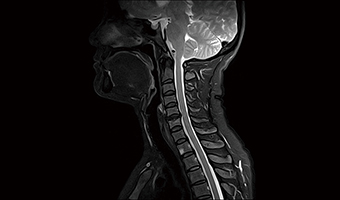

Uygulama Görüntüleri